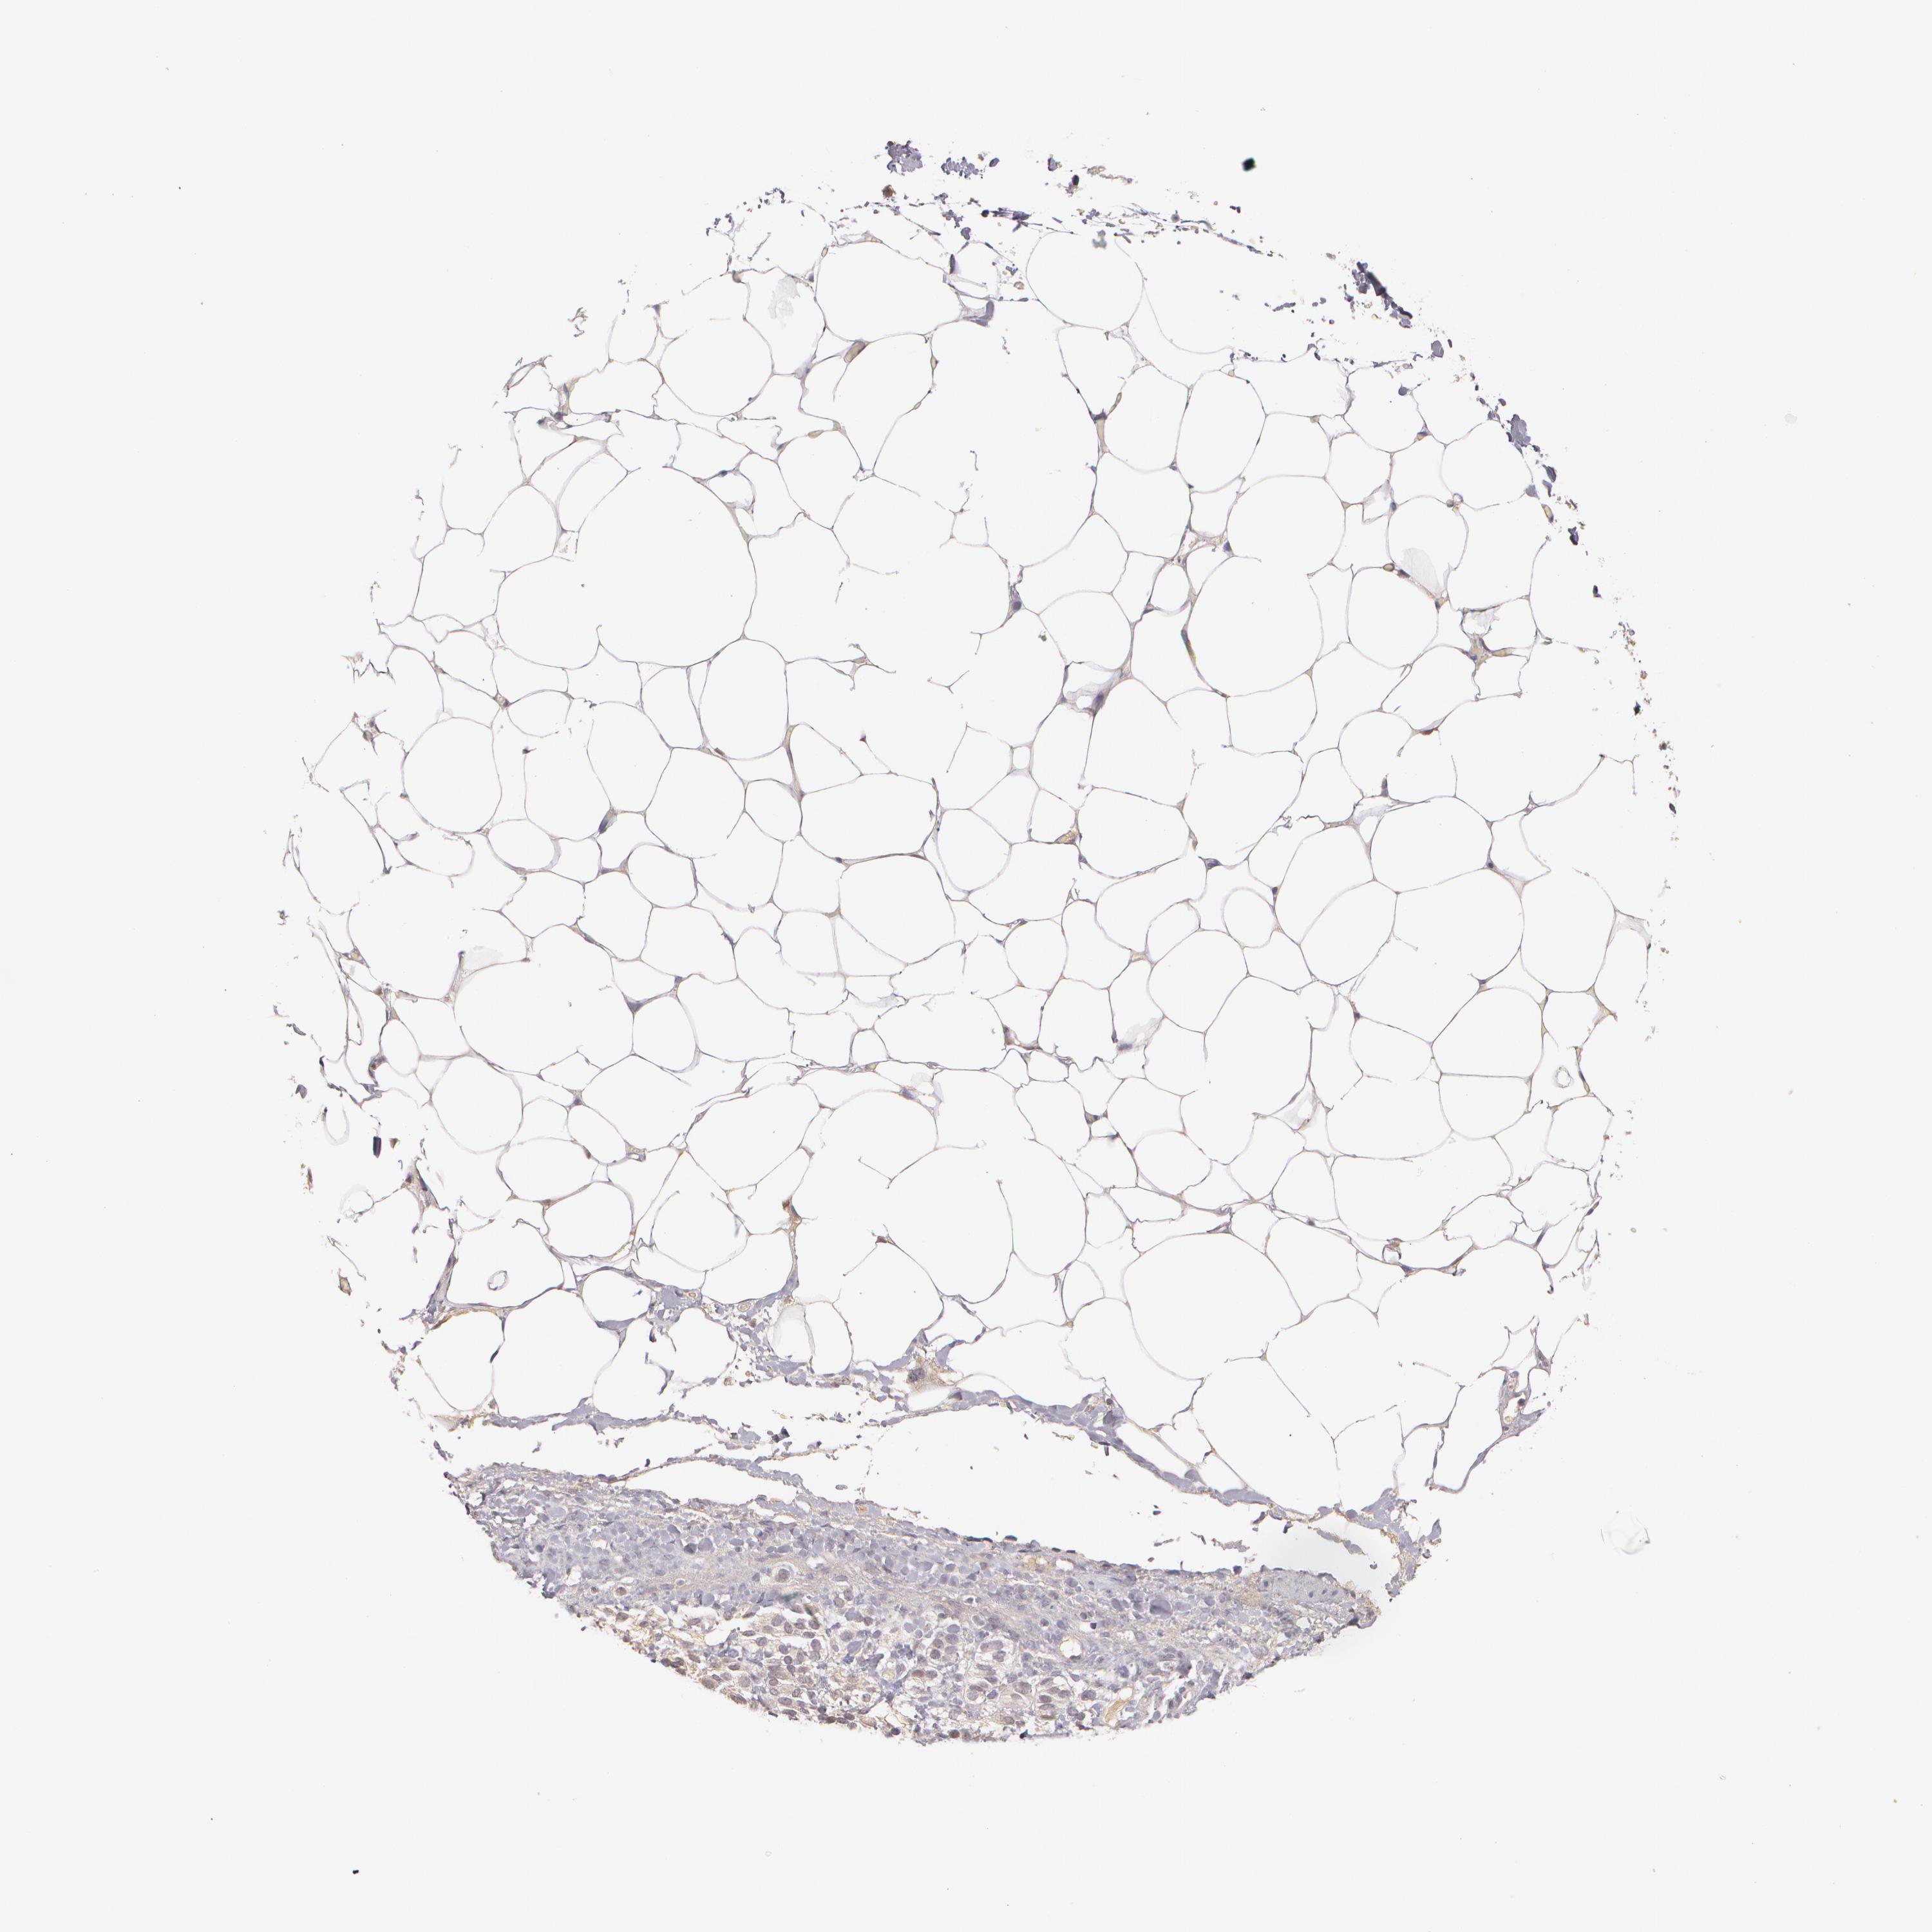

ADRENAL GLAND - Antibody stainingi

Antibody staining in the annotated cell types in the current human tissue is reported as not detected, low, medium, or high, based on conventional immunohistochemistry profiling in selected tissues. This score is based on the combination of the staining intensity and fraction of stained cells.

Each image is clickable and will lead to virtual microscopy that enables deeper exploration of all samples and also displays staining intensity scores, fraction scores and subcellular localization as well as patient and tissue information for each sample.

Antibody HPA001888Antibody HPA001889

Glandular cells Not detectedNot detected